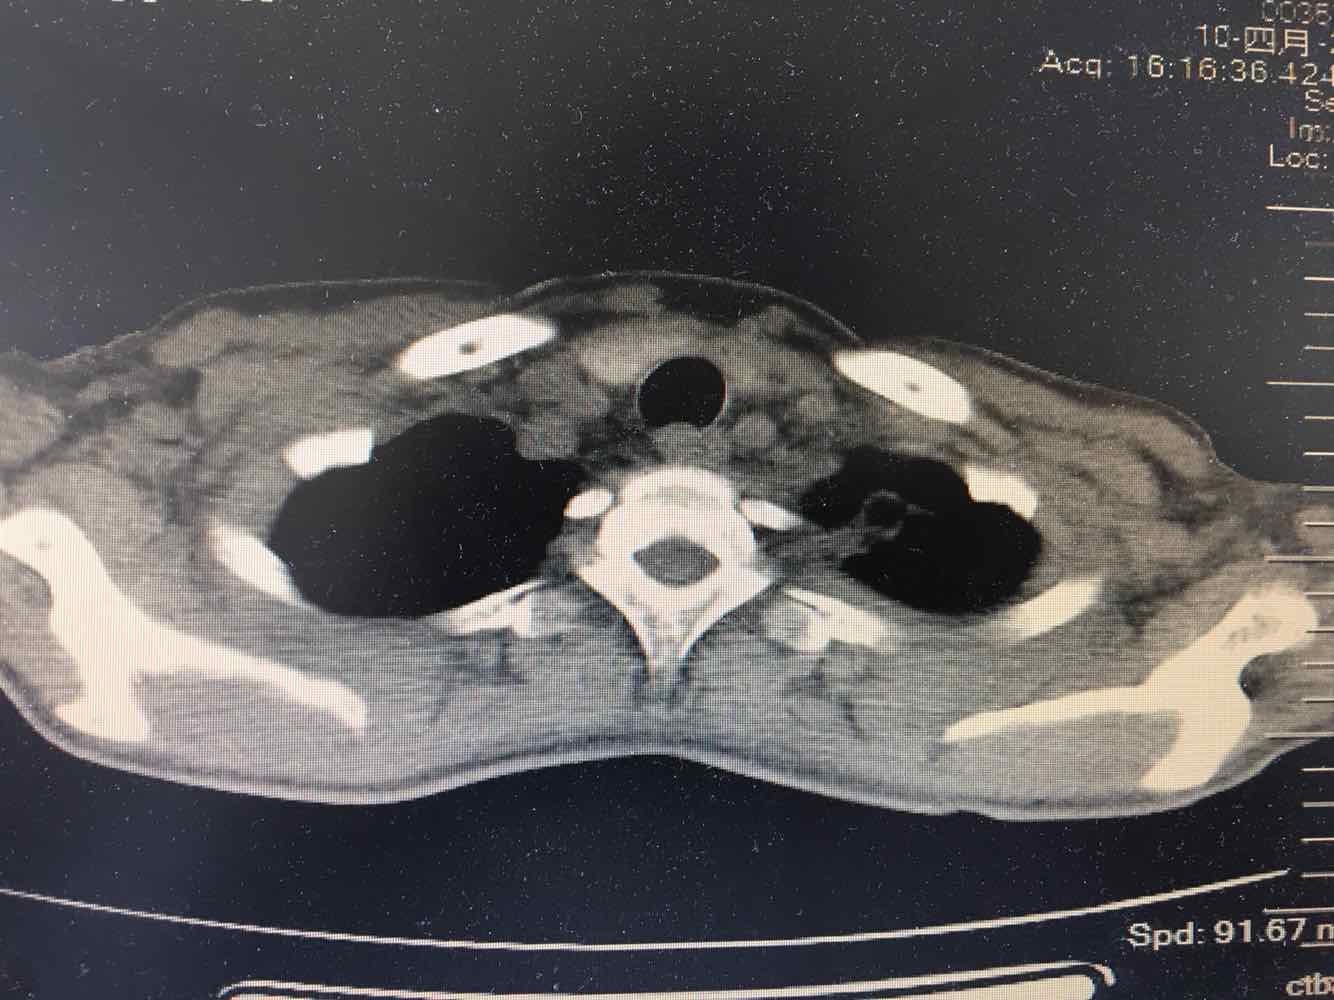

女,51岁,支气管扩张病史多年。慢性咳嗽咳痰喘息30年,加重1个月,无发热,气短为主,痰液不多,上腹不适,少尿。双肺干湿罗音。

图片

慢性肺源性心脏病

1/7

2/7

3/7

4/7

5/7

6/7

7/7